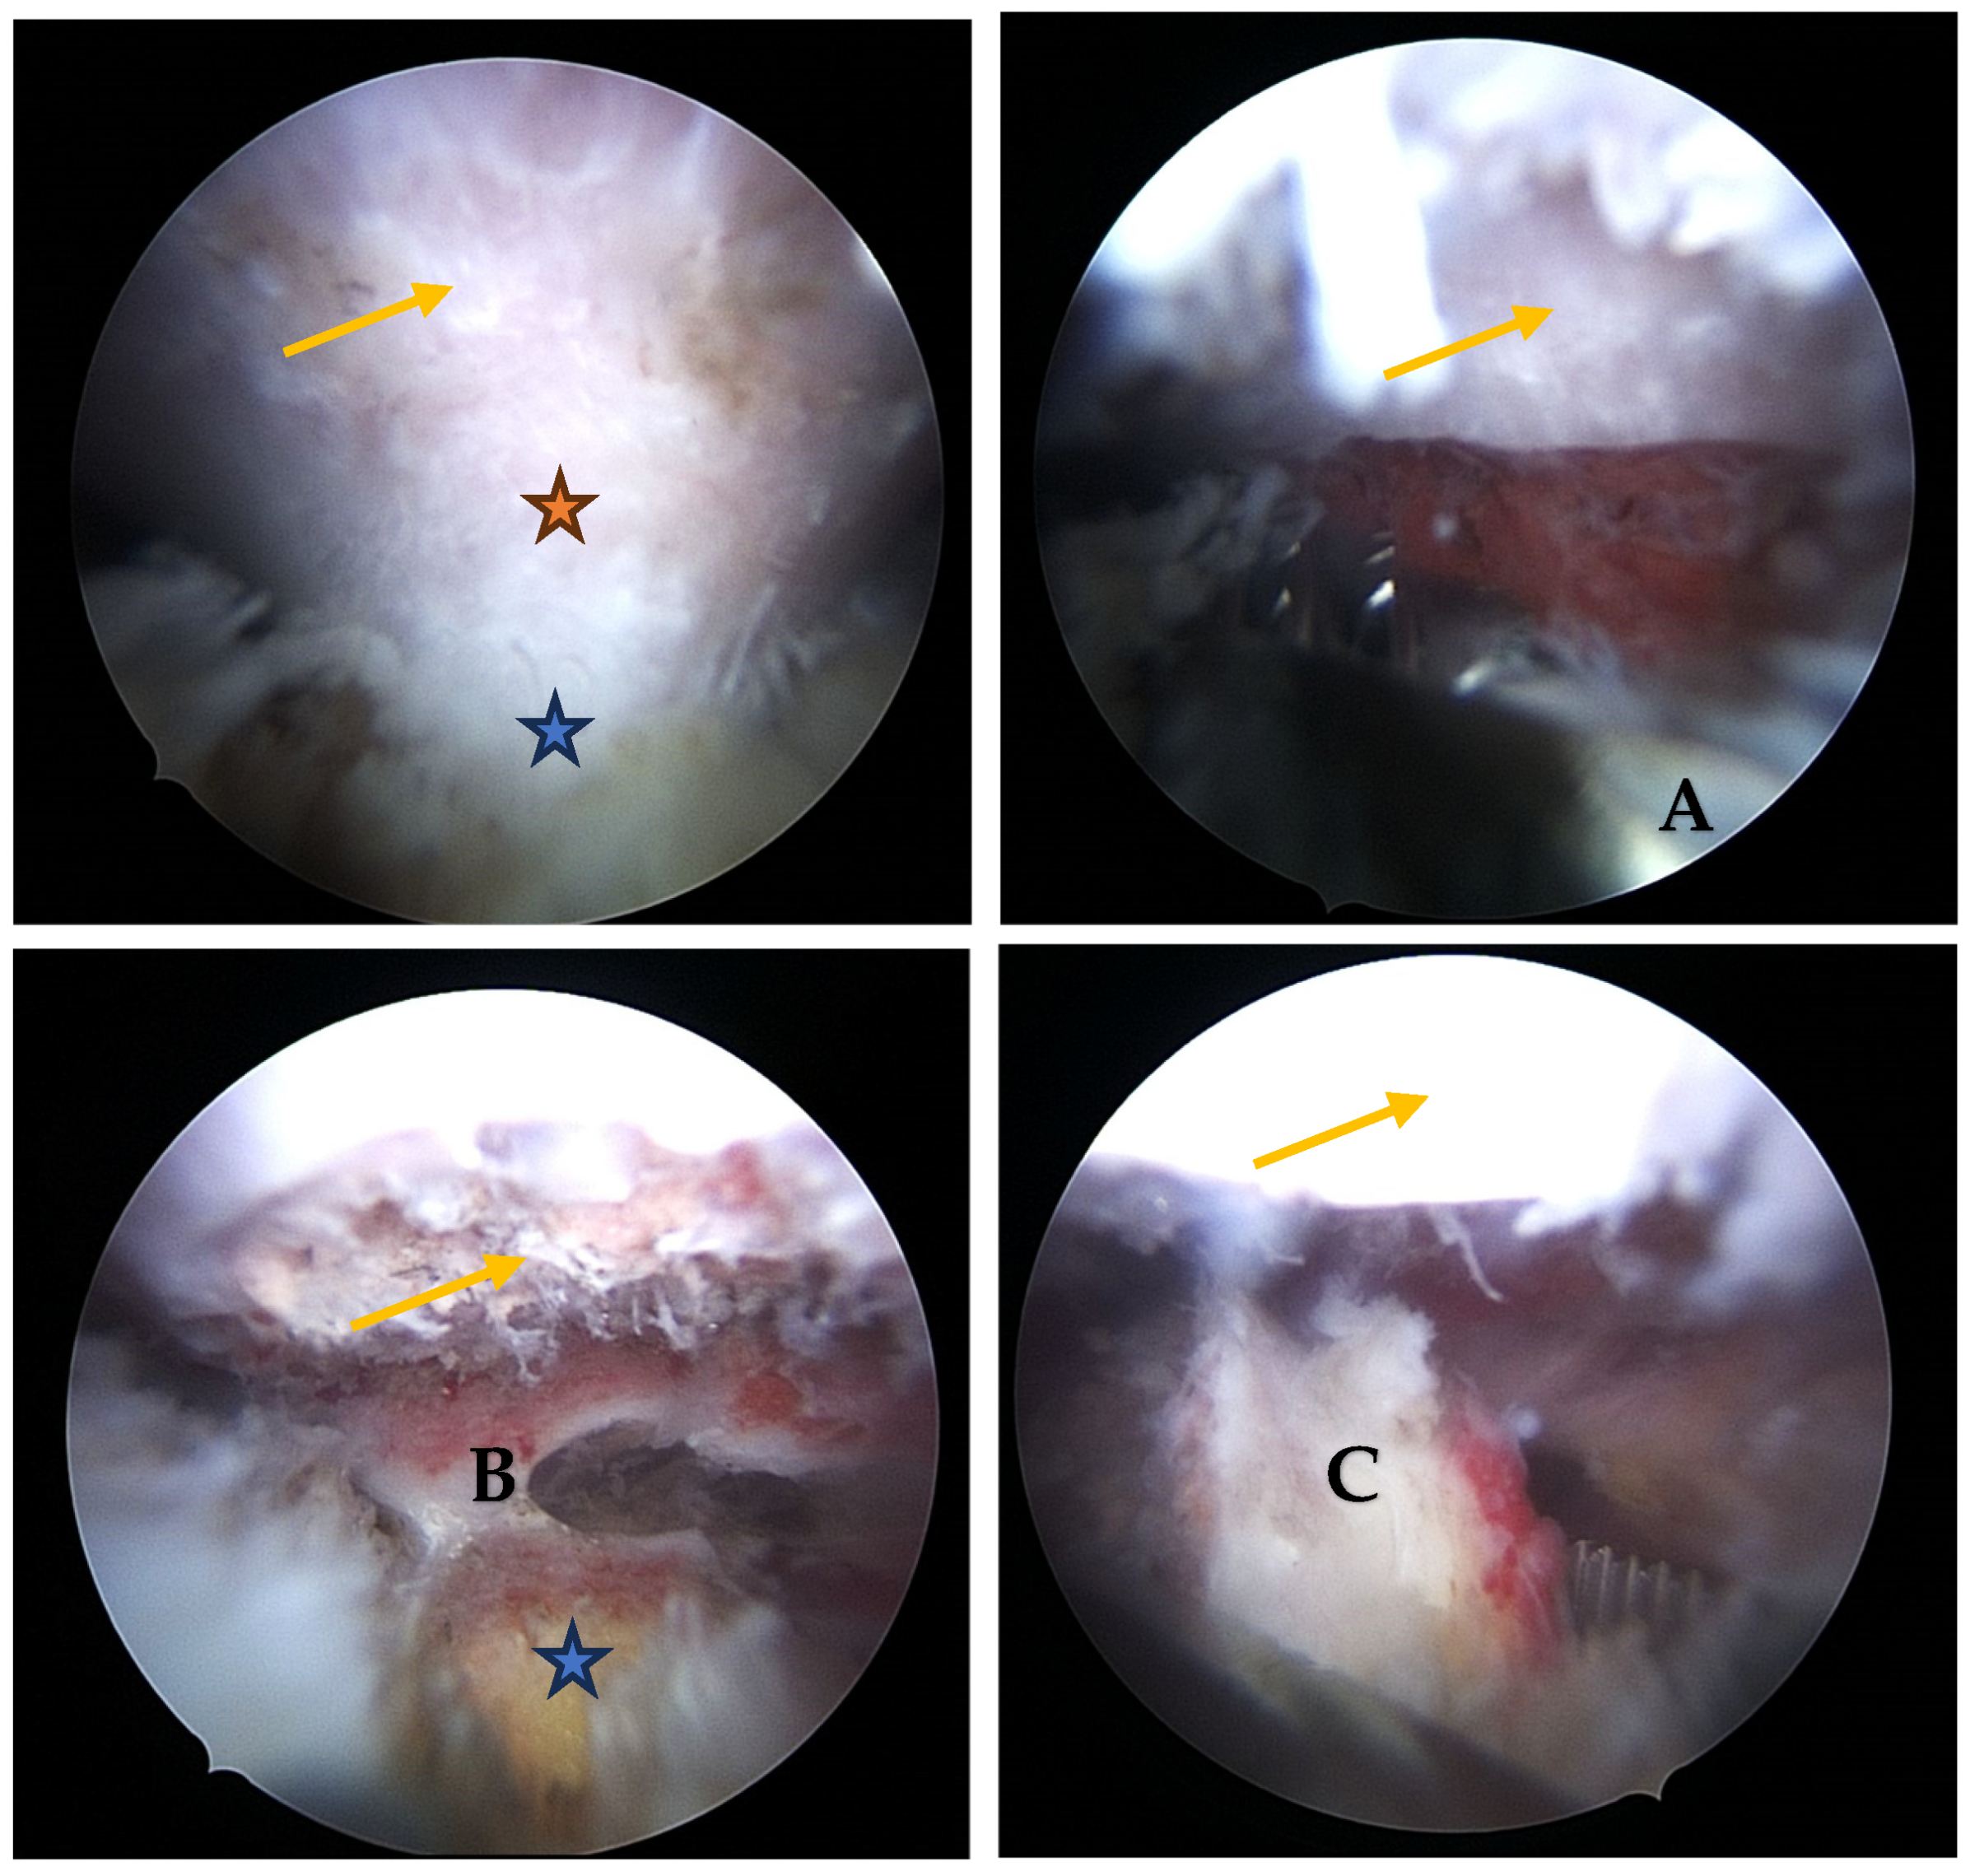

- Visualization: The arthroscope is introduced through the posterior portal. Initial visualization targets the inflamed scapulothoracic bursa to gain orientation (Figure 3A,B). In the present case, the exostosis was partially protruding through the subscapularis muscle and thus visible upon entry. A blunt dissection plane is established between the scapula and the subscapularis muscle to expose the exostosis base.

- Resection: Using a high-speed burr under continuous irrigation, the lesion is carefully resected flush to the scapular surface. To ensure oncologic safety, the exostosis is excised at its base as a single piece and removed using an arthroscopic grasper for histopathological examination (Figure 4). Constant visualization is maintained to avoid iatrogenic injury to adjacent structures.